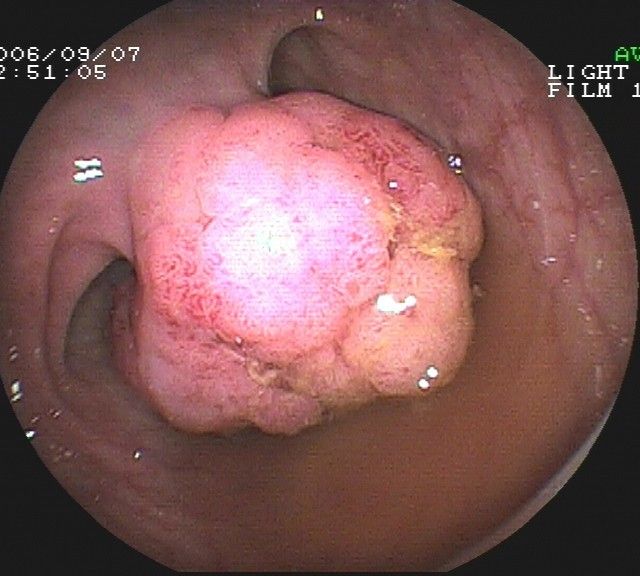

Coloskopie - riesiger rasenförmiger Polyp